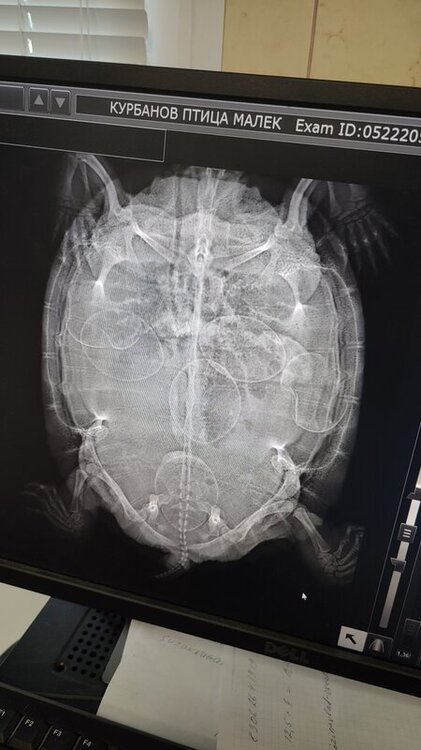

У меня 2 красноухих черепахи, самец и самка. Самка перестала есть, начала сидеть на суше, стала апатичной и начала часто дышать ртом и так уже примерно пятый-шестой день. Думал пневмония и отвёл к ветеринару, он сделал рентген (фото приложены) и оказалось, что она беременна, врач сказал что она открывает рот, потому что  тужится и яйца слишком большие и нужно делать кесарево и дал мне номер телефона клиники, где смогут сделать операцию, там назвали цену за операцию 15-20 тысяч рублей, и у меня сейчас нет таких денег. Тяжело смотреть на девочку, выглядит будто она мучается, не хочет есть и вообще почти не двигается, кроме головы, она ее вытягивает и набирает воздуха.